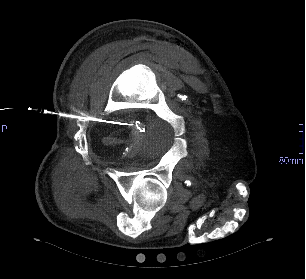

Needle, guidewire, sheath and catheter could all be placed into the seminal vesicle as demonstrated by CT-Imaging (Figure 3 [Fig. 3]). The guidewire coiled within the lumen of the seminal vesicle and we did not achieve to steer the guidewire through the ejaculatory duct to achieve a through-and-through access to the penile urethra. Therefore, we were not able to proceed to insertion of a balloon-catheter over the guidewire in a subsequent retrograde approach.

Figure 3: A 17 mm maximum intensity projection of a CT-Scan shows a guide-wire coiled within the lumen of the right seminal vesicle and an angiographic catheter sheath inserted into the seminal vesicle.